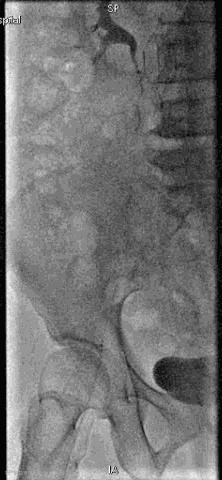

手术过程

抽吸结果